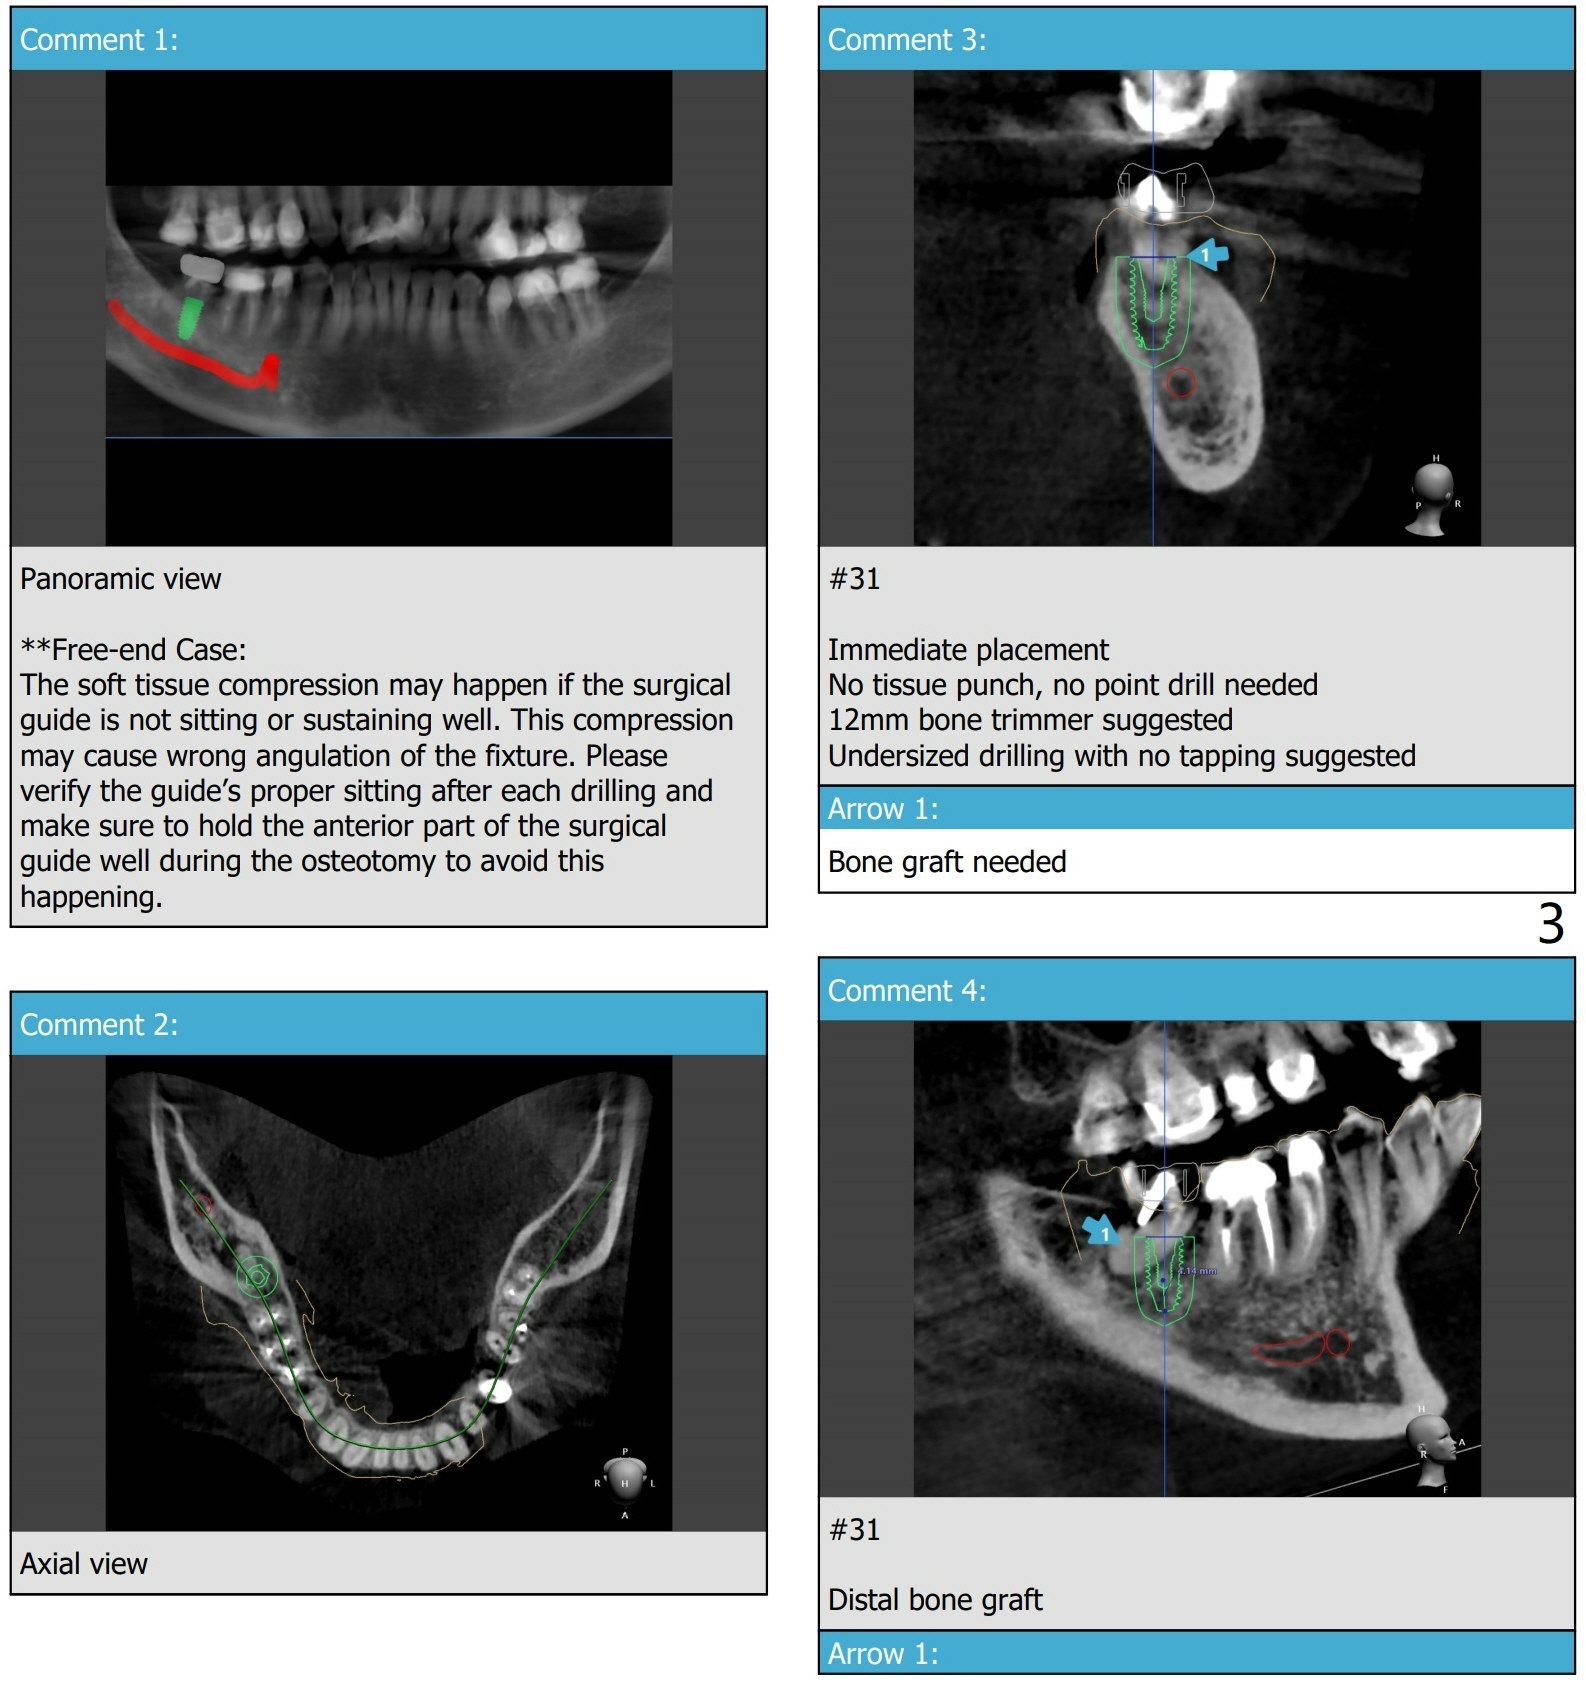

Mesial Slope

A 62-year-old woman

Return to Prevent Molar Periimplantitis (Protocols, Table) Protect Graft Metronidazole 下齿槽神经

Xin Wei, DDS, PhD, MS 1st edition 05/26/2021, last revision 08/10/2021